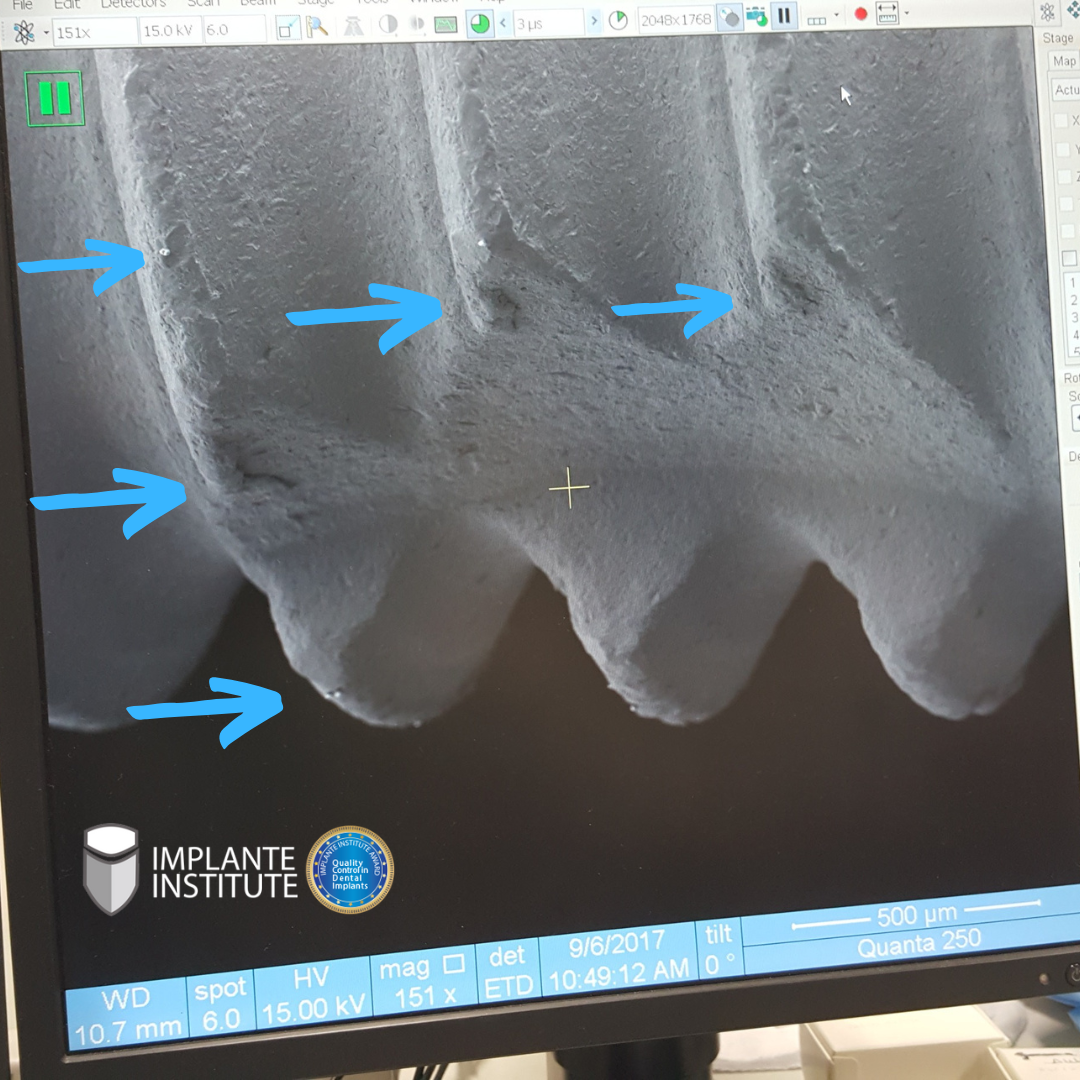

Superfície com pouca rugosidade e apresentando contaminações e rebarbas.

The surface is slightly rough and shows contamination and burrs.